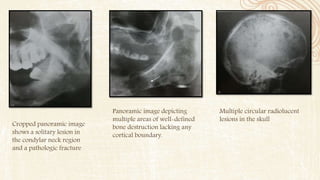

Multiple circular radiolucent

lesions in the skull

Panoramic image depicting

multiple areas of well-defined

bone destruction lacking any

cortical boundary.

Cropped panoramic image

shows a solitary lesion in

the condylar neck region

and a pathologic fracture

RADIOGRAPHIC FEATURES • Lesionsare bilateral,well-defined but not corticated radiolucencies,with an oval or a cystic shape –punched out appearance. It may appear ragged and even infiltrative. • The inferior alveolar canal looses its cortical boundary. The mandibular lesions cause thinning of lower border of mandible or endosteal scalloping.

Multiple circular radiolucent lesionsin the skull Panoramic image depicting multiple areas of well-defined bone destruction lacking any cortical boundary. Cropped panoramic image shows a solitary lesion in the condylar neck region and a pathologic fracture